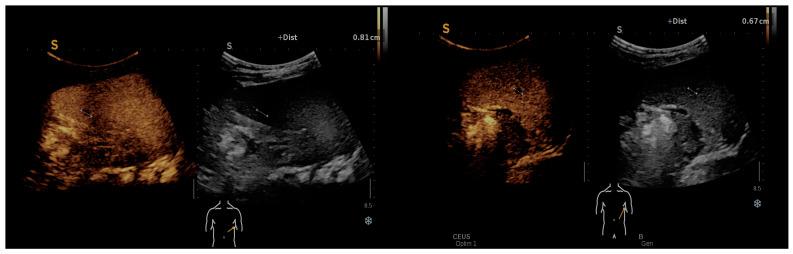

Systemic infection, also known as cat-scratch disease (CSD), presents a diagnostic challenge due to the variability of clinical manifestations and the potential for serological cross-reactivity with other organisms. This study aimed to retrospectively analyze the epidemiological, clinical, laboratory, and imaging characteristics of pediatric patients diagnosed with systemic infection, to improve understanding and facilitate timely diagnosis and treatment. We conducted a 10-year retrospective study at the "Louis Turcanu" Children's Emergency Hospital and private clinics in Timisoara, Romania, reviewing records for confirmed cases of infection from January 2014 to January 2024. The study adhered to the Declaration of Helsinki and received approval from the Institutional Review Board. Diagnostic criteria included contact with animals, prolonged fever, hematological and/or hepatosplenic manifestations, and positive serological tests for . Nineteen pediatric patients were identified with a median age of 8.1 years. The majority were exposed to felines (94.7%), reflecting the disease's epidemiological profile. Clinical findings highlighted fever (47.4%), lymphadenopathy (78.9%), and less frequently, abdominal pain and headache (both 10.5%). Laboratory analyses revealed a mean hemoglobin of 12.6 mg/dL, WBC count of 13.1 × 10 cells/microliter, and platelet count of 340.6 × 10 per microliter. Significant findings included elevation in ESR and CRP in 47.4% and 21.1% of patients, respectively, and high seropositivity rates for IgM (63.2%) and IgG (94.7%). Imaging studies demonstrated widespread lymphadenopathy and occasional splenomegaly and hepatic microabscesses. All patients received antibiotic therapy, with azithromycin being the most commonly used (94.7%). Co-infections with Epstein-Barr Virus, Cytomegalovirus, and were documented, indicating the complex infectious status of the patients. Systemic infection in children predominantly manifests with fever and lymphadenopathy, with a significant history of exposure to felines. Laboratory and imaging findings support the diagnosis, which is further complicated by potential co-infections. Effective antibiotic therapy, primarily with azithromycin, underscores the need for comprehensive diagnostic and treatment strategies. This study emphasizes the importance of considering systemic infection in pediatric patients with prolonged fever and contact with cats, to ensure timely and appropriate treatment.